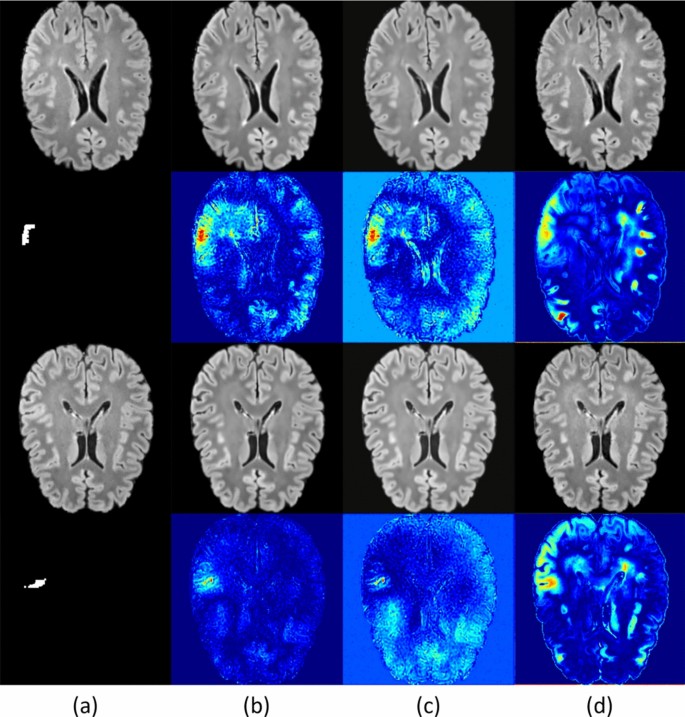

Comparison results with and without histogram matching. (a) is the original image, (b) is the result using modal transformation and using histogram matching, (c) is the result without using histogram matching, and (d) is the result without using modal transformation.

We conducted an ablation study to evaluate the effects of three critical components: positional information guidance, modal shift, and histogram matching. As detailed in Table 2, a diffusion model using only FLAIR modality guidance fails to integrate information from the T1 image, significantly reducing the detection of abnormal locations. The R@5 and R@10 were 0.301 and 0.726, respectively, which starkly contrast with the rates of 0.852 and 0.956 achieved using the T1 image. This limitation may impair the model’s accuracy in aiding physicians and increase the risk of misdiagnosis.

Incorporating positional information enhances the model’s ability to focus on areas with a high incidence of epileptic lesions by utilizing knowledge of brain deconvolution. This addition led to improved recall rates, increasing by 0.13 and 0.096 compared to scenarios without location information. Although the Dice score decreased by 0.045, recall metrics are more crucial for providing physicians with pertinent information during diagnosis. Therefore, prioritizing a higher recall score over maintaining the Dice score is justified. Histogram matching further reduces the likelihood of overlooking lesions due to color variations, demonstrating its effectiveness with recall improvements of 0.329 and 0.027 and Dice score enhancements of 0.101. The visualization of these results is presented in Fig. 4.